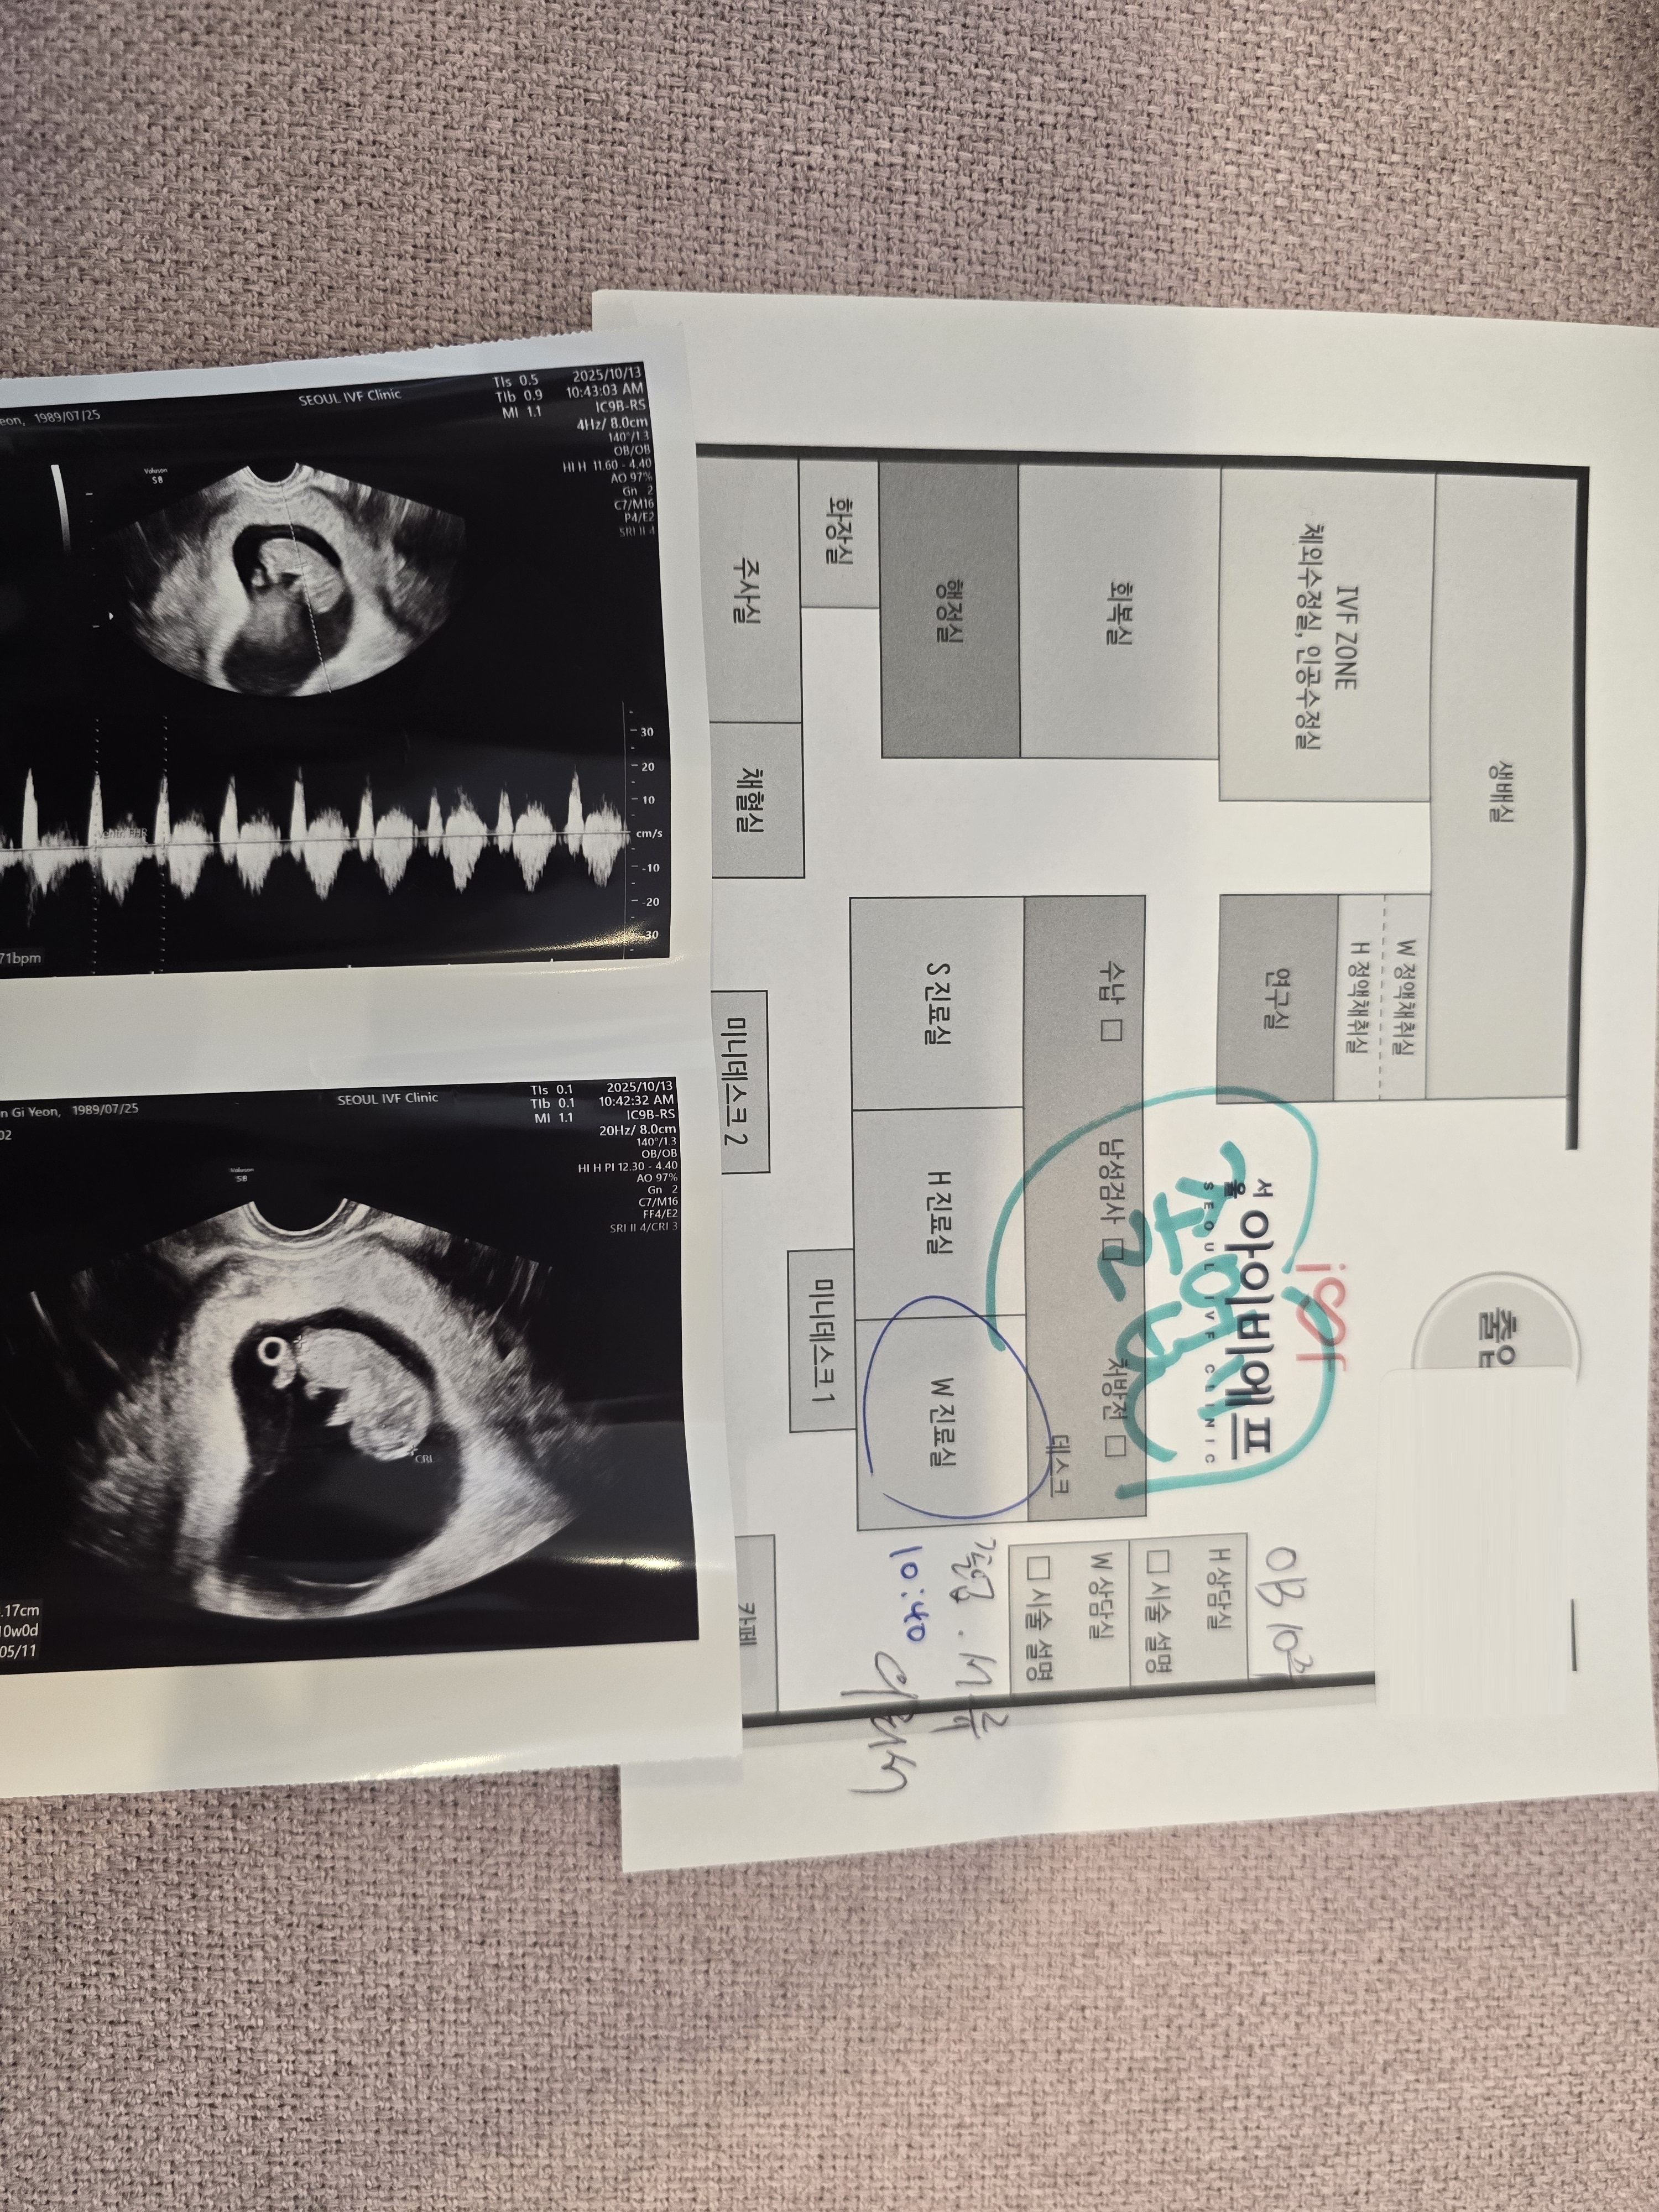

| 가슴 떨리는 임신 이야기를 공유해 주세요. | 앞선 두 번의 실패 후 병원을 옮겨보기로 한 뒤 서울아이비에프에서 이유정 원장님과 난임 치료를 다시 시작하게됐어요 그리고 성공 소식을 들었고 너무 기뻤습니다. |

| 서울IVF여성의원의 난임 치료에 대해 말씀해 주실 것이 있나요? | 이유정 원장님께서 너무 친절하시고, 성공할 수 있는 방법을 직접 찾아주시면서 맞춰 치료해주셔서 정말 감사했어요. 마음이 편안해지는 병원이었습니다. |